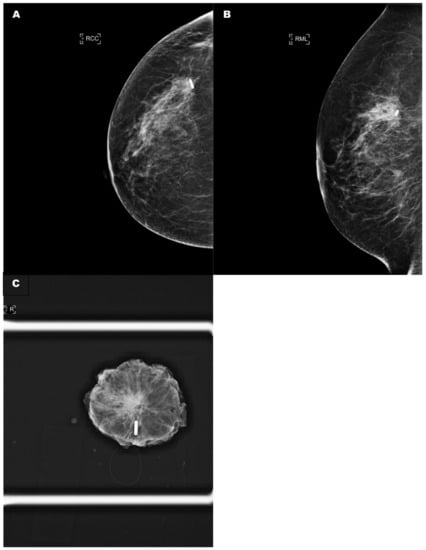

Figure 3.

(A) A control craniocaudal mammography film showing the radio-frequency tag within the tumour. (B) A control oblique mammography film showing the radio-frequency tag within the tumour. (C) A specimen radiograph demonstrating that the radio-frequency tag had migrated by 1 cm along the needle introducer track. RCC: right craniocaudal; RML: right medialateral.